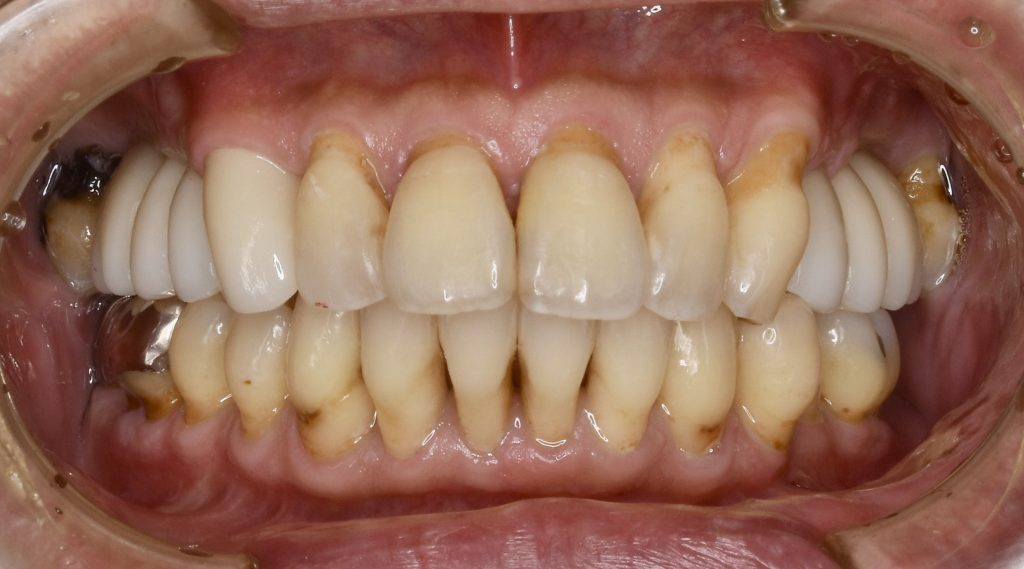

下記の症例は上顎臼歯部(上の奥歯)の骨量が不足している症例に対し、難易度の高いサイナスリフトを行い、骨量を改善させたのちインプラント埋入を行いました。

当医院では、このような難易度の高い手術を若手に指導する立場ですので、安全で確実、長持ちした歯科治療をお受けになられたい方は是非一度ご相談にいらしてください

上記の症例にかかる費用 約430万円(税抜)